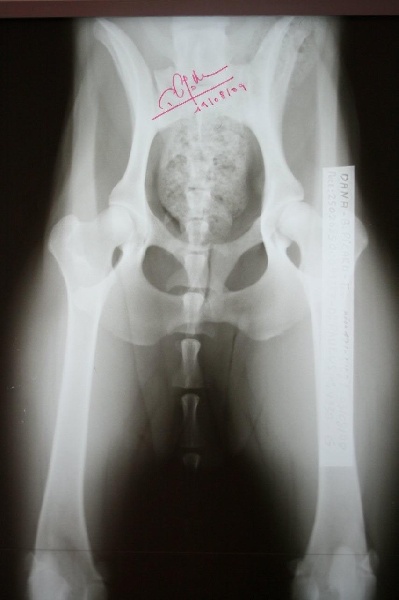

Radio officielle A/A

Dysplasie : A / A MANQUE : AUCUNE T O : INDEMNE |